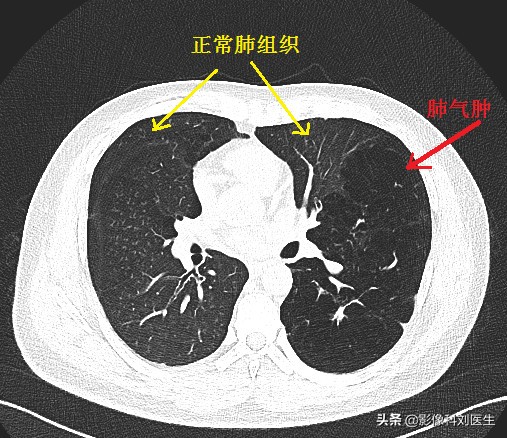

首先给大家看几张CT图像:

通过上面的图像,相信大家有了一个大概的印象。肺气肿主要征象即为正常肺组织内出现无囊壁的低密度区。